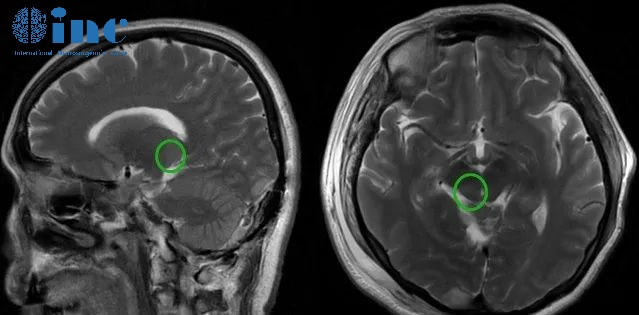

2022年12月1日,我于蘇州市獨(dú)墅湖醫(yī)院接受巴教授主刀的手術(shù)。術(shù)后影像顯示,巴教授近全切腫瘤。

高難度丘腦膠質(zhì)瘤術(shù)后患者自述——術(shù)后影像

術(shù)后1天ICU時(shí),巴教授查房,這讓我安心。他還用中文輕聲詢問”你感覺怎么樣“。而我也如實(shí)回答,“我感覺很好,術(shù)前評(píng)估說的可能出現(xiàn)的復(fù)視、手麻都沒有,感謝巴教授。”

術(shù)后4天巴教授查房,我已恢復(fù)基本正常,可以自己下床走動(dòng)。“恢復(fù)得挺好的,沒有什么不舒服的地方”,我也和教授交流我的情況。